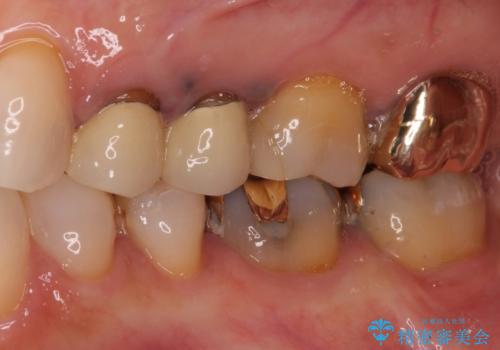

- 歯肉が退縮したためにクラウンの縁や歯根が見えてしまっていることを気にして来院された患者様です。

また、歯肉が黒く変色していることも気になるとのことでした。

仮歯に変える際に歯肉の一部を切除し、金属片による変色を除去した後、オールセラミッククラウンにて補綴することとしました。

メタルタトゥー(金属イオンの溶出による歯肉の変色)は、歯に装着された金属から金属イオンが溶け出したり、金属を除去するときの切削片が歯肉に入り込んでしまったりして引き起こされます。

物理的に除去をすることできれいな歯肉となりますが、残留している金属イオンにより再発するリスクがあります。